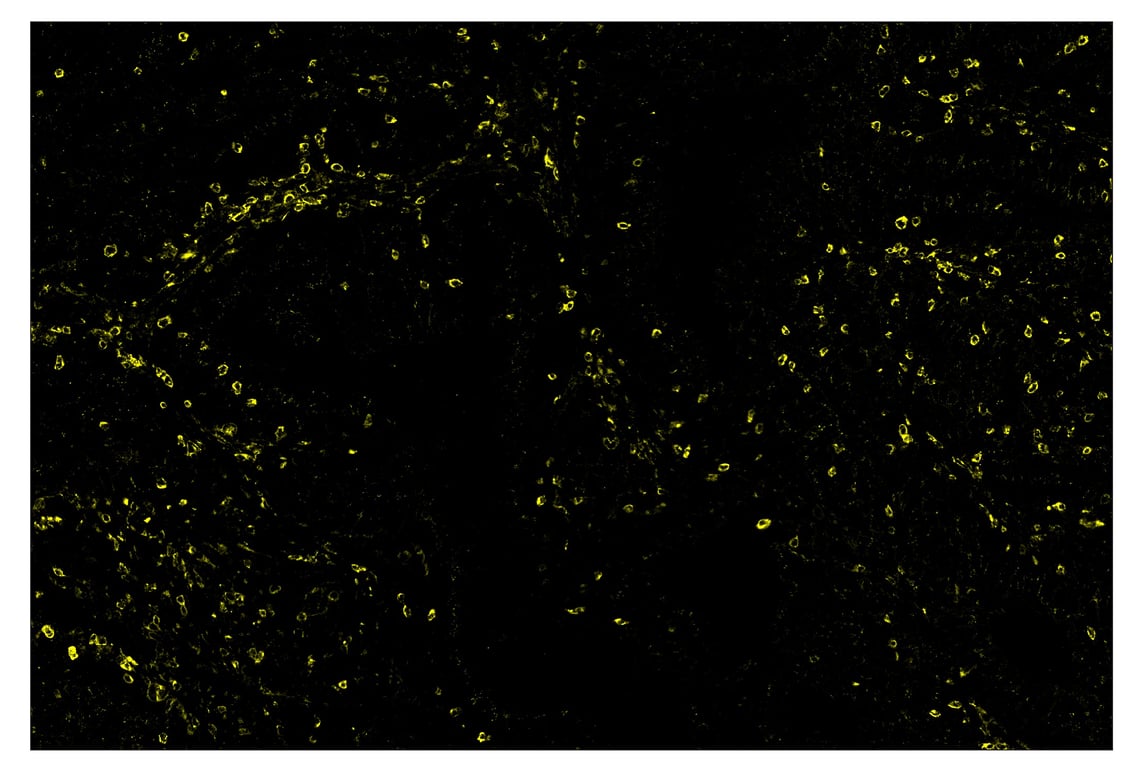

SignalStar™ immunohistochemical analysis of paraffin-embedded human colorectal adenocarcinoma using TIM-3 (D5D5R™) & CO-0010-594 SignalStar™ Oligo-Antibody Pair #55508 (yellow). All fluorophores have been assigned a pseudocolor, as indicated. Staining was performed on the BOND RX by Leica Biosystems.

Immunohistochemistry Image 3: TIM-3 (D5D5R<sup>™</sup>) & CO-0010-750 SignalStar<sup>™</sup> Oligo-Antibody Pair